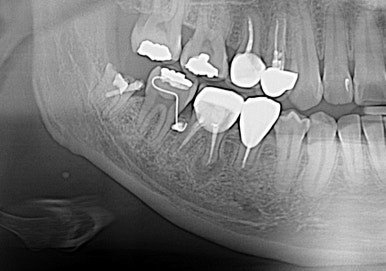

그렇다.. 그래서 손상의 가능성을 줄이고 줄여보자해서 ....

사랑니 뿌리가 신경관과 근접

교정력을 주어 열심히 당기기 한 달 별다른 위치변화가 보이지 않아서 좀 답답하다...